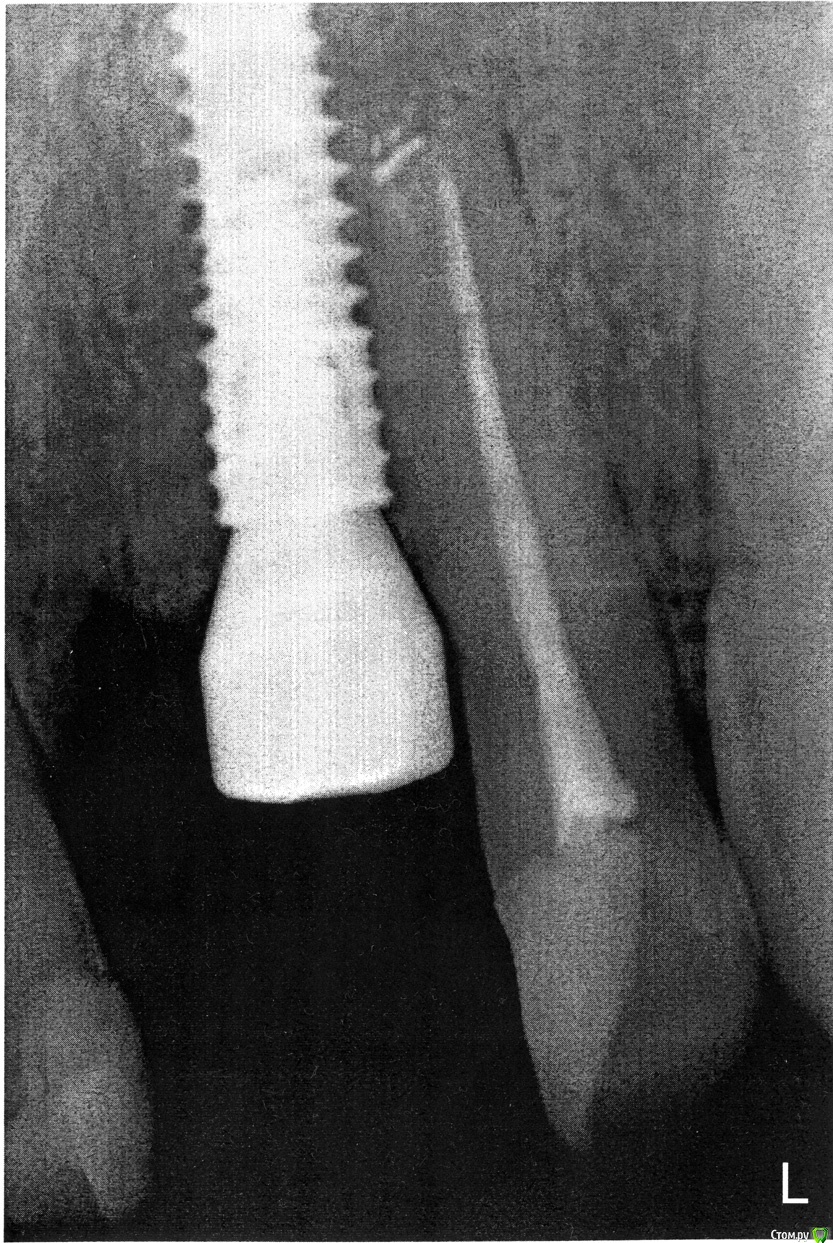

nickk Опубликовано 7 октября, 2020 Автор Поделиться Опубликовано 7 октября, 2020 По просьбам выкладываю свежий прицельный снимок.По состоянию на данный момент, спустя 5 недель после операции:Остаются эпизодические кратковременные тянущие ощущения где-то высоко над 21-22 зубом. Не во время еды, само по себе. Насколько это нормально при приживающимся импланте не знаю - первый мой опыт. В целом потянуло и отпустило, не критично, но и ведь без нагрузки. Не будет ли хуже?Так же бывают (не всегда) тянущие ощущения под нагрузкой где-то над 22 зубом. Не боль, но тянет. При простукивании зуба - неприятных ощущений нет.Так же присутствуют не глубокие (по локализации) болезненные ощущения при осторожной чистке щёткой 22зуба, по ближней кромке зуба к формирователю (торец зуба).Припухлость (отёк) десны без изменеий, если она есть (см. фото) мне трудно судить, я просто сравниваю что с лева и с права. Ссылка на комментарий

Марья Моревна Опубликовано 7 октября, 2020 Поделиться Опубликовано 7 октября, 2020 (изменено) К сожалению, на снимке не видно участок верхушки имплантата.Перед тем,как решать вопрос окончательно,я бы сделала еще снимок немного в другой проекции (левее) или КЛКТ сегмента. Изменено 7 октября, 2020 пользователем Марья Моревна 1 Ссылка на комментарий

Марья Моревна Опубликовано 8 октября, 2020 Поделиться Опубликовано 8 октября, 2020 Слишком близко к зубу (на той проекции, которая представлена). Ссылка на комментарий

Irouil Опубликовано 8 октября, 2020 Поделиться Опубликовано 8 октября, 2020 Исходя из присутствующей симптоматики (которой в норме не должно быть), позиции имплантата в соотношении с соседним зубом и в соотношении с идеальной позицией будущей коронки я бы этот имплантат удалил - чем раньше, тем лучше 2 Ссылка на комментарий

red_butler Опубликовано 8 октября, 2020 Поделиться Опубликовано 8 октября, 2020 Почему? Мне бы хотелось бы получить более развёрнутые ответы, для разговора с хирургом, что не так.В первую очередь из-за позиции импланта, он находиться слишком высоко и близко к зубу Ссылка на комментарий